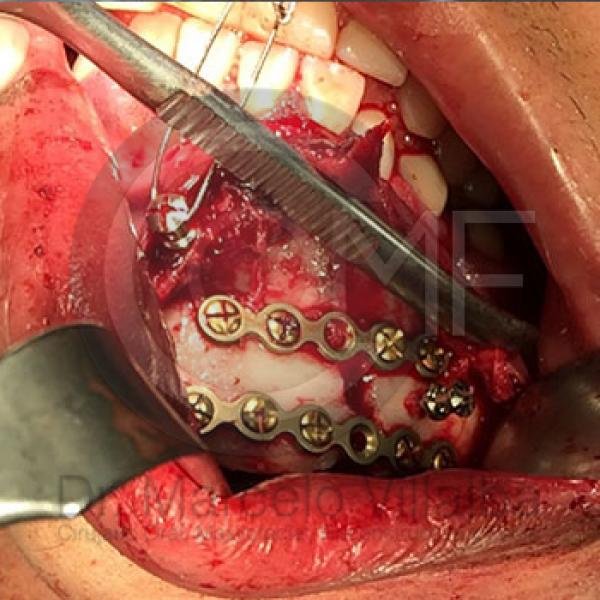

La Cirugía Oral y Maxilofacial es una de las especialidades odontológicas que brinda la posibilidad de ofrecer soluciones medicas y quirúrgicas a diferentes problemas de salud, entre los que se encuentran los defectos congénitos como el labio y paladar fisurados, las disarmonias del desarrollo facial, los traumatismos y lesiones patológicas de la región oral y maxilofacial por mencionar algunos; utilizando distintos procedimientos como la Cirugía Ortognática, la Reconstrucción mediante toma y colocación de injertos, distractores osteogénicos, regeneración tisular, implantes, etc.

CIRUGÍA ORTOGNÁTICA EN DEFORMIDADES O ASIMETRÍAS FACIALES

Es una cirugía en la que se busca mover el maxilar, mandibular y mentón o sólo una de estas estructuras para alcanzar una combinación médico-odontológica, así llegar al fin estético y funcional del aparato estomatognático y facial.

Contenido Sensible y Gráfico

Si usted no pertenece al área de la salud, las imágenes pueden ser muy explícitas.